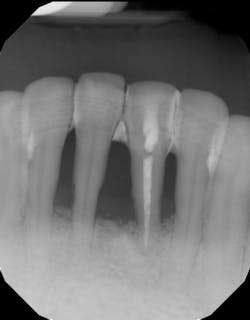

- Ensure tooth does not have a root fracture and check/refer for endodontic treatment if tooth is nonvital (figure 1)

A large, randomized controlled trial of 50 patients presenting with advanced bone loss and at least one hopeless tooth to be extracted due to periodontal bone loss were enrolled in a study. The hopeless teeth evaluated had bone loss to or beyond the apex of the tooth. Twenty-five hopeless teeth were periodontally treated with a regenerative strategy, and 25 teeth were extracted and replaced with either a fixed bridge or a dental implant. Two teeth in the “save the teeth” group were lost in the first year. At the end of five years, the remainder of the teeth in the “save the teeth” group (23 out of 25 regenerated teeth) showed clinical improvement. Clinical attachment level gains were around 8 mm, radiographic bone gain around 8.5 mm, and probing depth reduction about 9 mm. Residual pocket depths around the once-hopeless teeth were about 4 mm.9

This same group was then evaluated for another five years of the 10-year study. All teeth not lost after the first year (23 out of 25) were still present and remained clinically stable. The 10-year clinical attachment gain was 7 mm, residual pockets were about 3.5 mm, and saving the teeth was a less costly alternative to tooth extraction and replacement.